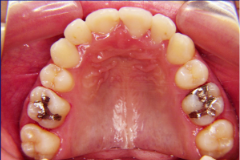

装置装着前

装置装着後